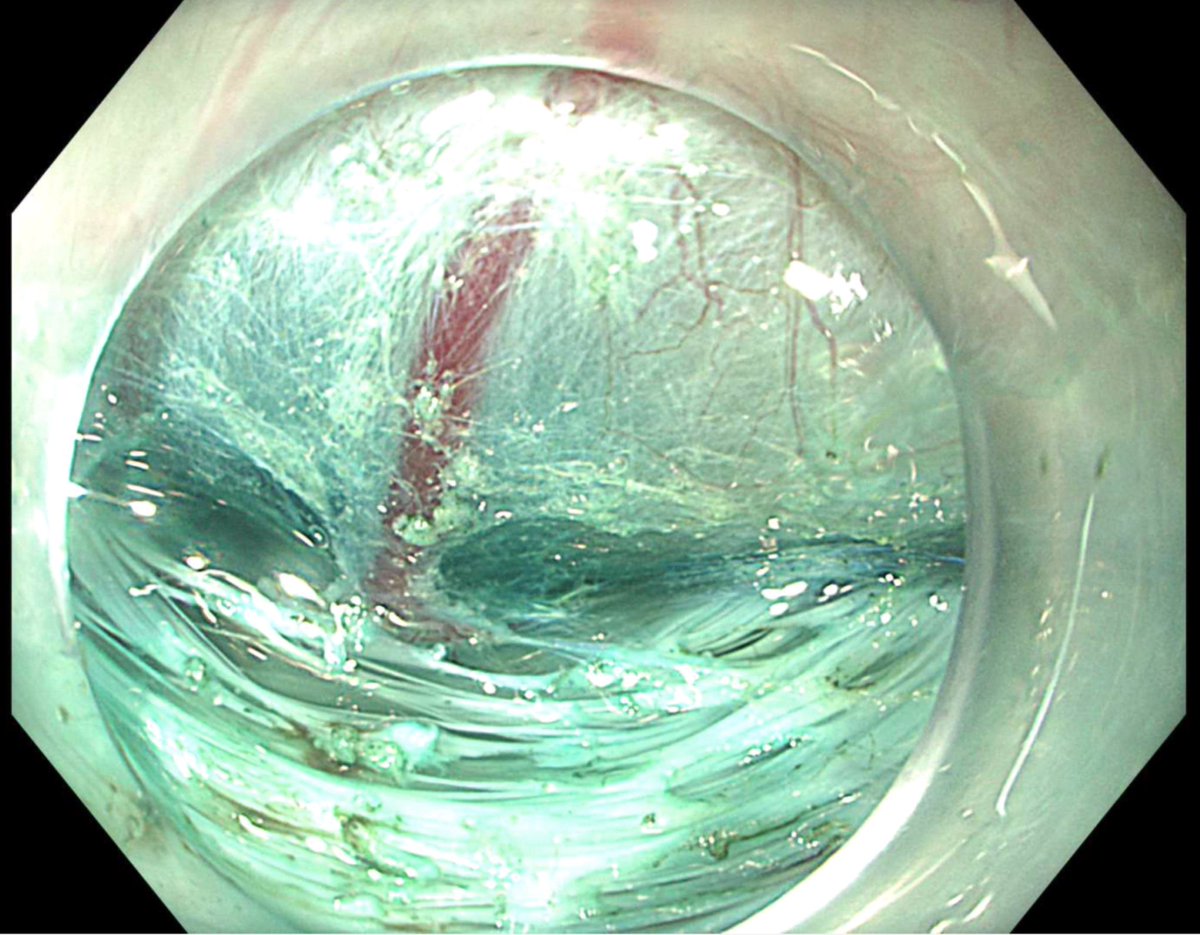

اما العملية الجراحية التي تجرى في حالات الاكاليزيا هي Heller myotomy و يقابلها من حيث الفعالية اجراء يجرى عن طريق المنظار و دون الحاجة لاجراء شق في البطن هي POEM و هي اختصار ل Peroral Endoscopic Myotomy و التي اثبتت فاعليتها في حل المشكلة بنسب عالية جدا.

هذه صور لاحدى الحالات التي اجريت في المستشفى الجامعي و التي بحمد الله تكللت بالنجاح بواسطة المنظار عن طريق اجراء فتحة صغيرة لا تتجاوز ٢ سم في المريء.